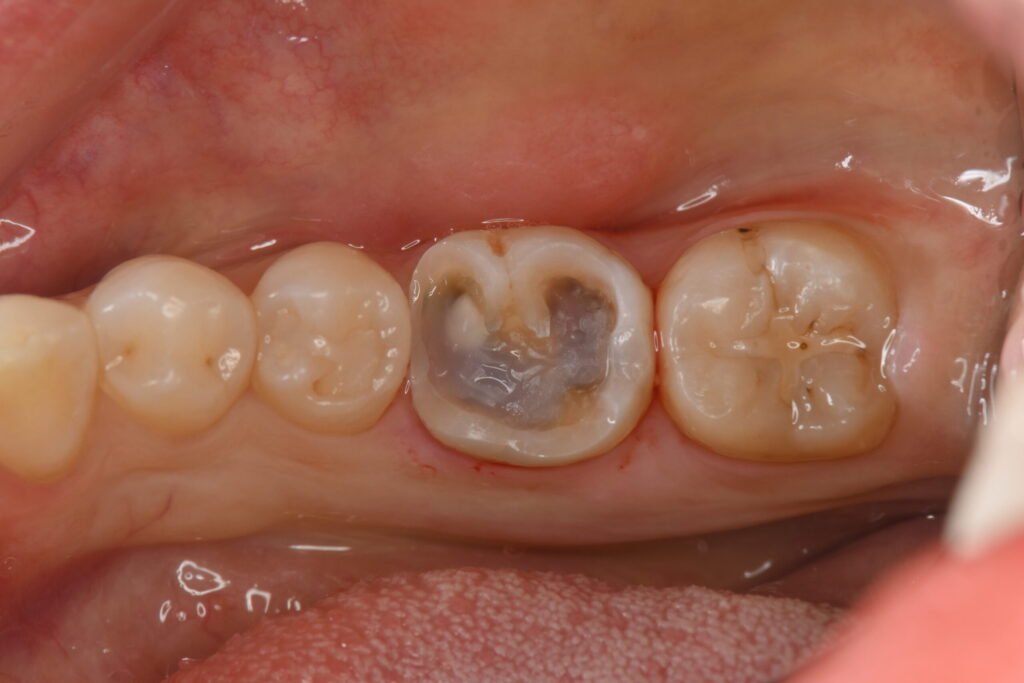

過去に別の歯科医院にて銀歯の詰め物がされており、その下で虫歯が再発していた症例です。

レントゲン検査にて銀歯の下に虫歯の再発が見つかったため、治療の選択肢(保険・自費)とそれぞれのメリットデメリットをお話ししたところ、虫歯の再発のリスクを少しでも抑えたいとのことで自費治療のご希望に変更されました。

この大きさの虫歯は、通常全体を削って被せることでセラミックが割れるリスクを減らすのですが、ご本人様のご希望もありできるだけ歯を削らずに白矢印部を残す形でセラミック(オーバーレイ)を作成しました。